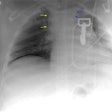

OBJECTIVE. The purpose of this study was to show that helical CT could be used at our

center in lieu of routine aortography to examine patients who have had serious blunt chest

trauma. We also wanted to assess the potential savings of using CT to avoid unnecessary

aortography. MATERIALS AND METHODS. The institutional review board approved the parallel

imaging-CT immediately followed by aortography-of patients presenting with blunt chest

trauma between August 1997 and August 1998. To screen patients for potential aortic

injuries, we performed parallel imaging on 142 patients, and these patients comprised our

patient population. CT examinations of the patients were reviewed for signs of injury by

radiologists who were unaware of each other's interpretations and the aortographic

results. Findings of CT examinations were classified as negative, positive, or

inconclusive for injury. Aortography was performed immediately after CT. The technical and

professional fees for both transcatheter aortography and helical CT were also compared.

RESULTS. Our combined kappa value for all CT interpretations was 0.714. The aortographic

sensitivity and negative predictive value were both 100%. Likewise, the sensitivity and

negative predictive value of CT were 100%. The total costs of performing aortography were

estimated at approximately $402,900, whereas those for performing helical CT were

estimated at $202,800. CONCLUSION. Helical CT has a sensitivity and negative predictive

value equivalent to that of aortography. Using CT to eliminate the possibility of

mediastinal hematoma and to evaluate the cause of an abnormal aortic contour in a trauma

patient allows us to use aortography more selectively. Avoiding the performance of

unnecessary aortography will expedite patient care and reduce costs. We report the results

of our experience with CT and how our center successfully made this transition in the

initial examination of patients with serious thoracic trauma.